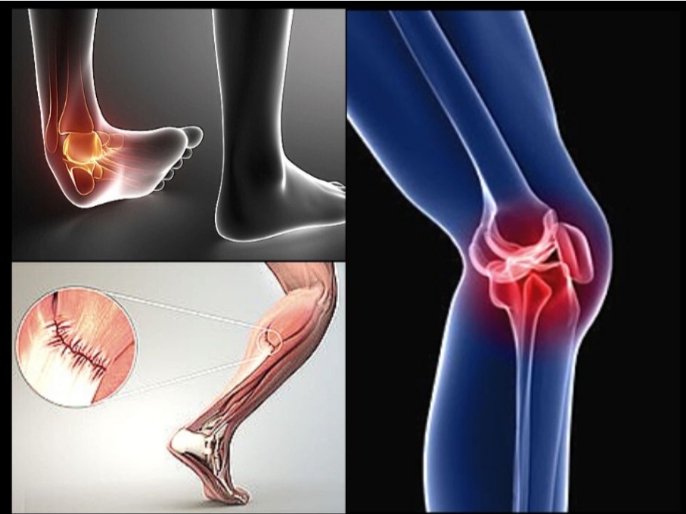

SPORTS INJURIES

Surgeon for sports injuries, knee injury, ACL Injury, Shoulder Injury.